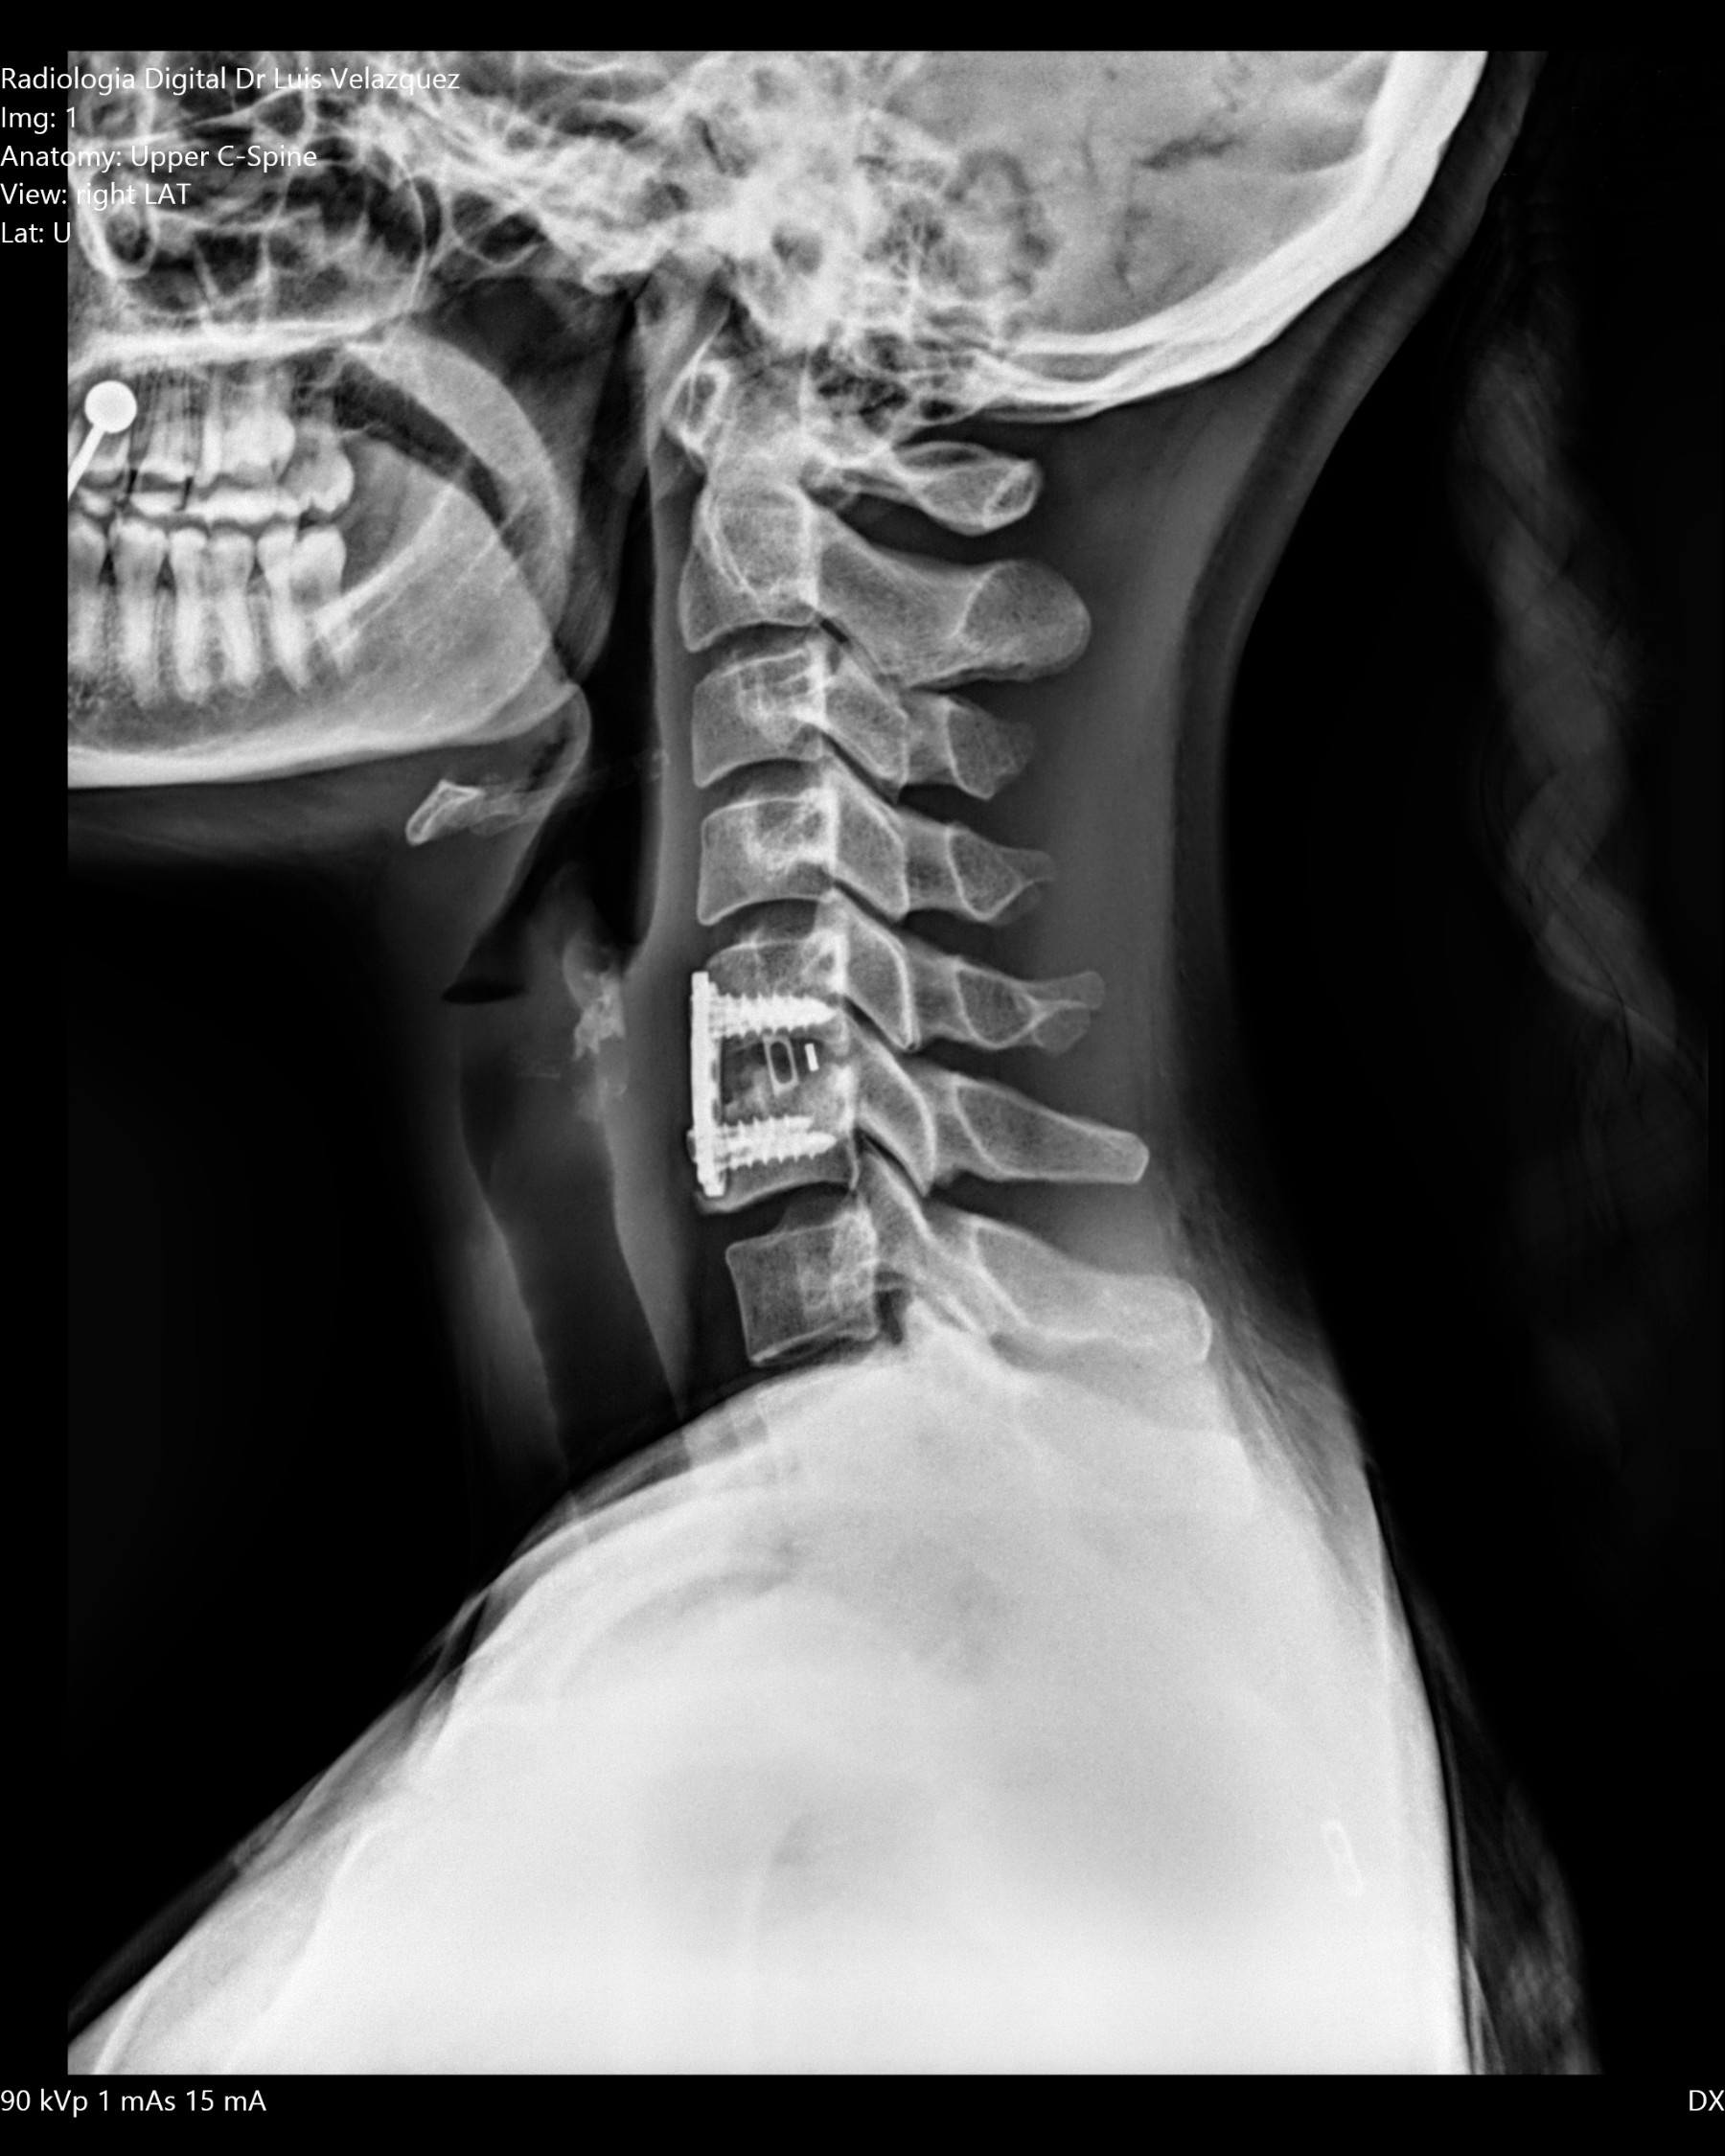

Radiología Digital como Herramienta Complementaria en el Dictamen de Bienes Muebles